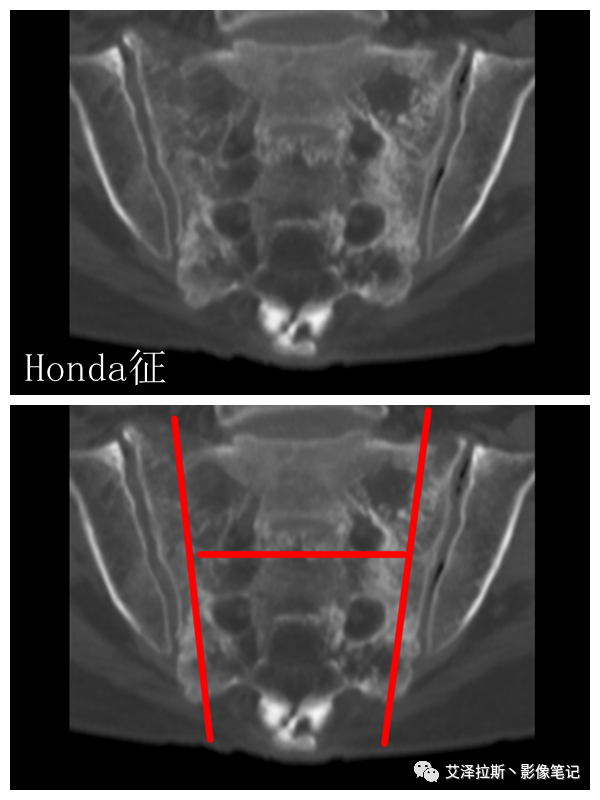

①单侧或者双侧骶骨翼骨折,典型者呈“H”形,即“Honda征”;

②骨折线位于骶孔外侧(如下图,主要发生于1区),通常可能会伴随耻骨的功能不全骨折(如:病例2 右侧耻骨上支骨折,L5双侧横突骨折);

MRI:

①表现同X线CT;

②骨折线周围见T1稍低T2、T2抑脂序列高信号,Gd-DTPA增强明显强化;